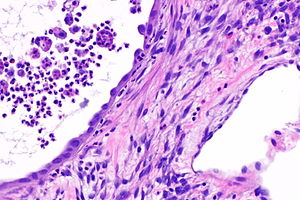

Micrograph of cystic nephroma (adult type) showing the characteristic stroma and hobnailed epithelium. H&E stain. | |

| LM | cysts lined by simple epithelium with hobnailing, stroma has an ovarian look (blue, spindle cells) |

- Cysts lined by simple epithelium with hobnailing - key feature.

- Stroma has an ovarian look:

- Blue (basophilic).

- Spindle cells.

- Parenchymal elements (e.g. glomueruli, tubules) are not found in the septa between the cysts.

The tumour is predominantly cystic. The cysts are lined by hobnail cells. Ovarian-like stroma is present.